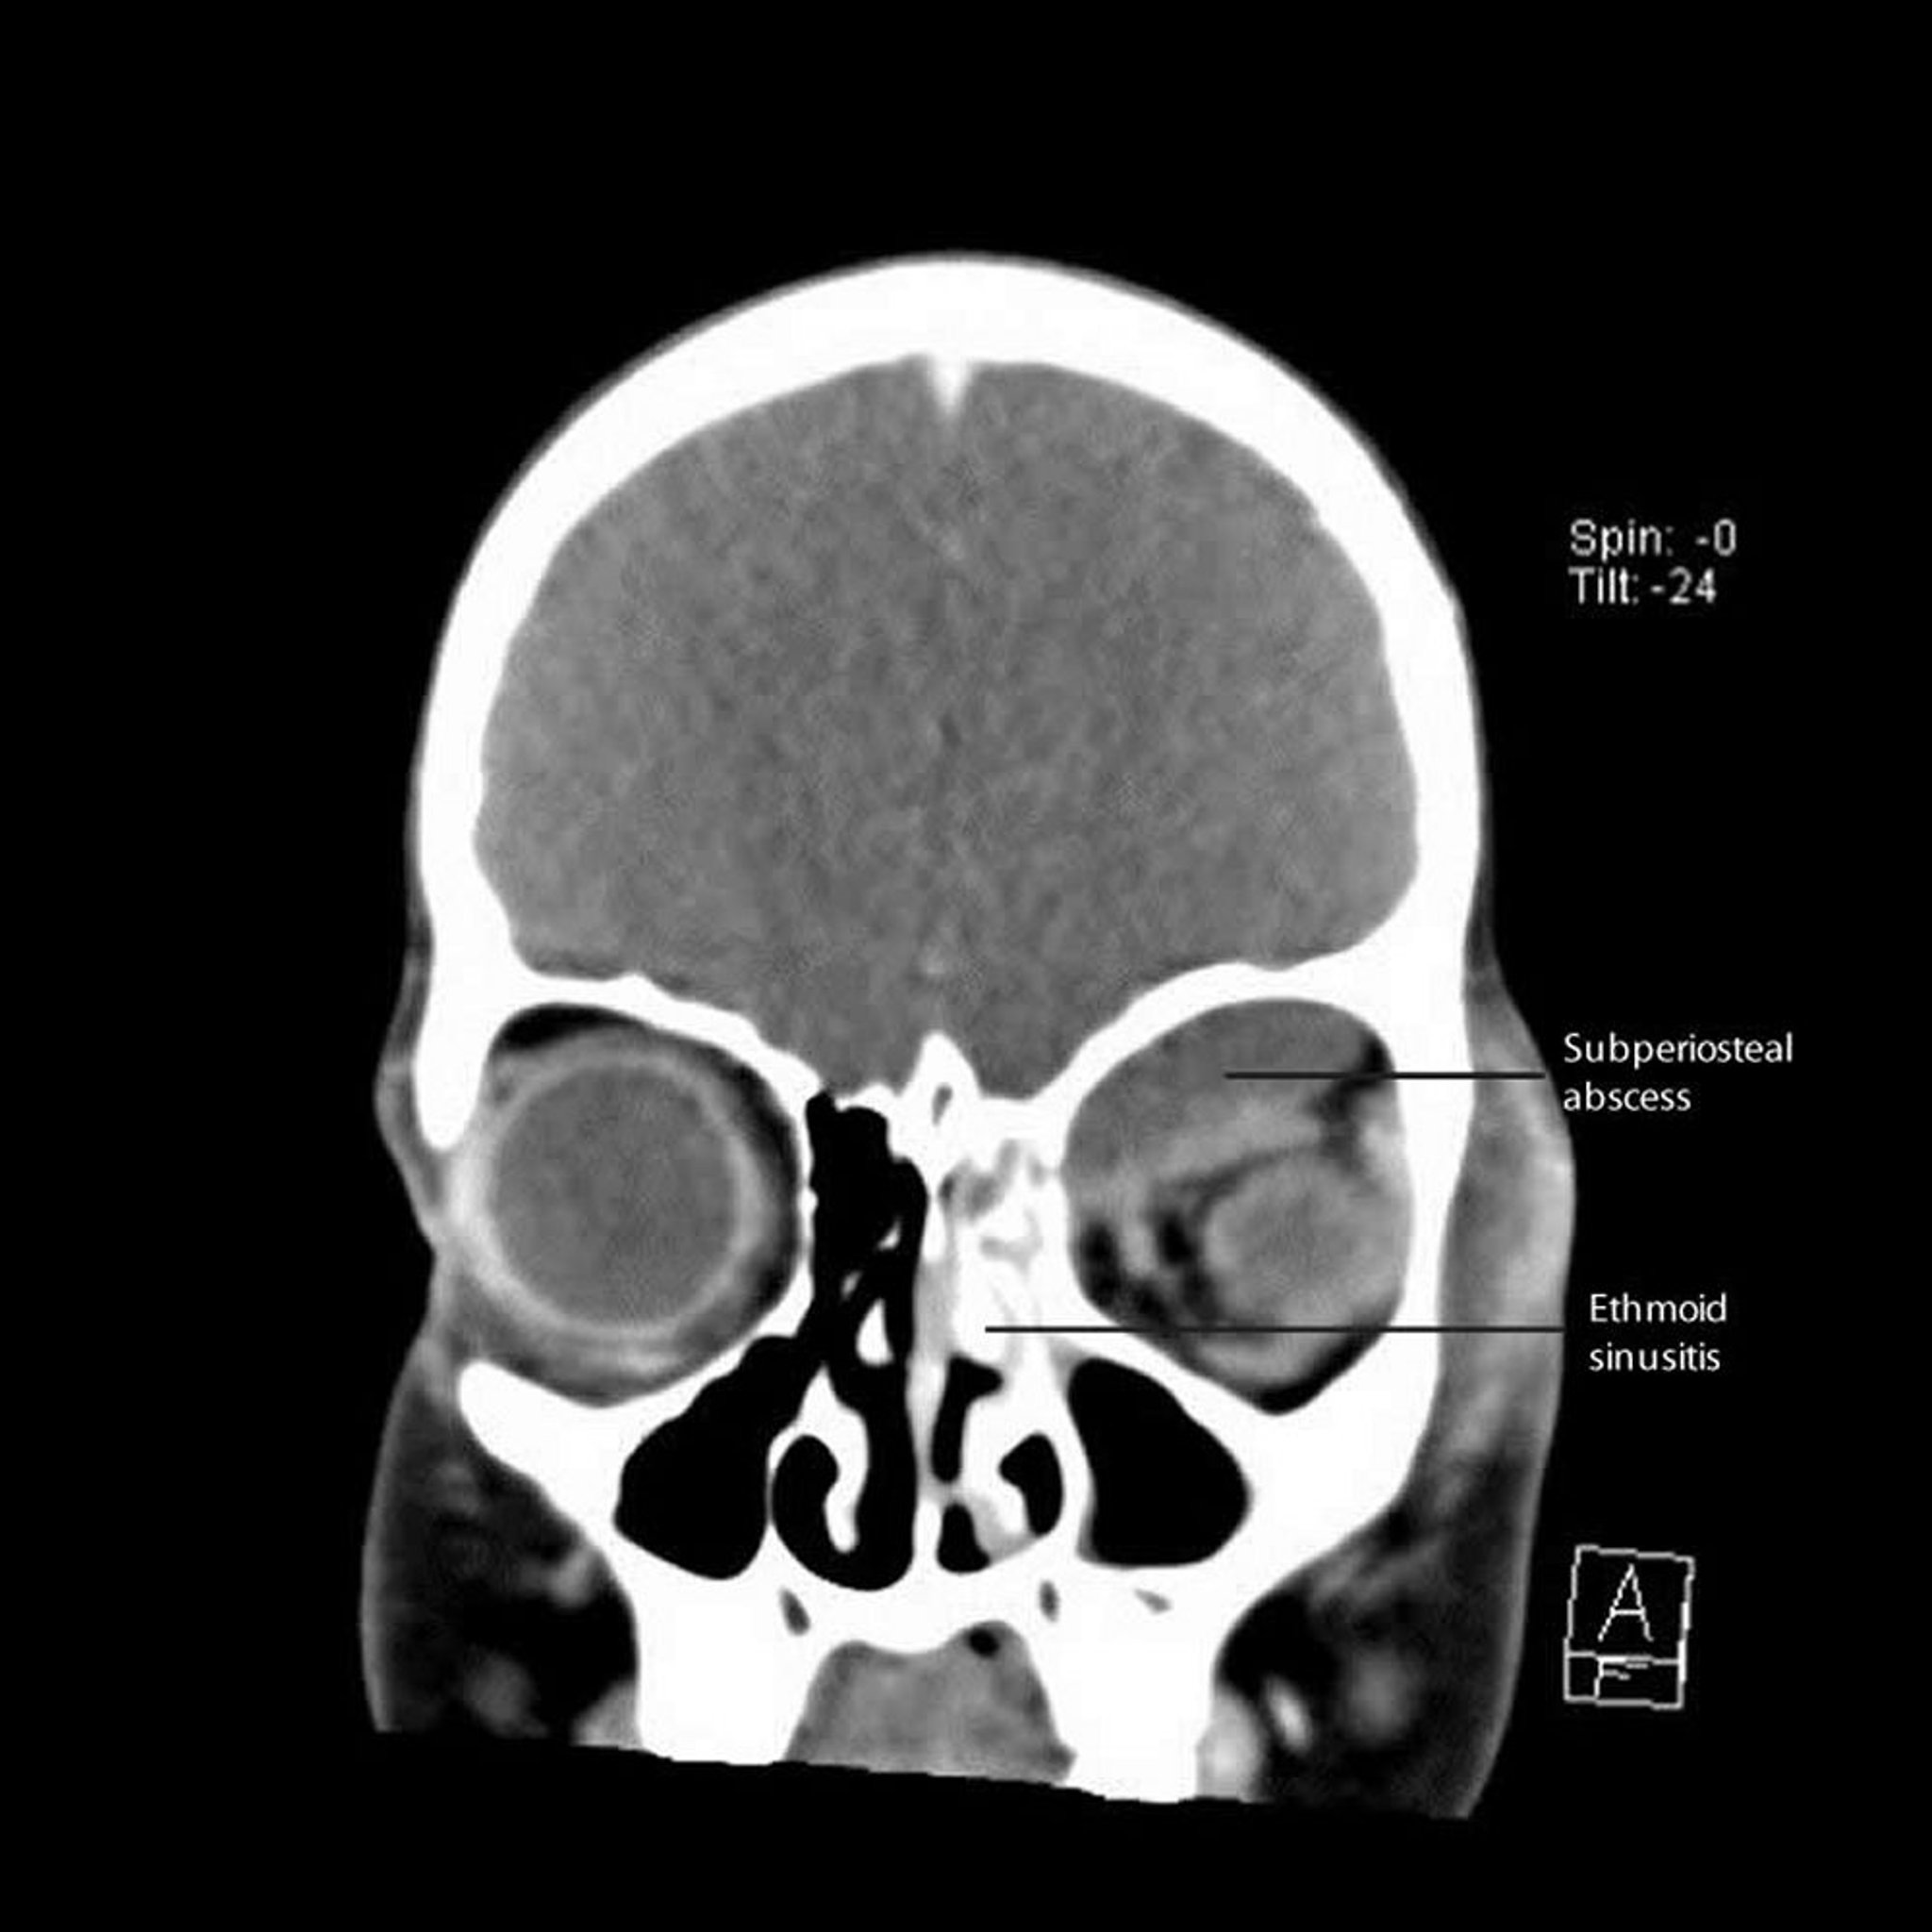

Pathophysiology of Preseptal and Orbital Cellulitis

Da die Orbitalphlegmone durch große benachbarte fulminante Infektionsherde (z. B. Sinusitis) entsteht, die nur durch eine dünne knöcherne Barriere getrennt sind, kann sich die Orbita großflächig und schwer infizieren. Es können subperiostale Flüssigkeitsansammlungen entstehen, die manchmal recht groß sind; sie werden als subperiostale Abszesse bezeichnet, obwohl viele zu Beginn steril sind.

Subperiostale Abszesse können, wenn sie groß genug sind, zu Beschwerden einer Orbitalphlegmone beitragen, wie eine Schwellung und Rötung des Augenlids, Einschränkung der Augenbeweglichkeit, Exophthalmus und Visusreduktion.

Bei mehrdeutigen Befunden, einer schwierigen Untersuchung (wie bei kleinen Kindern) oder Vorhandensein von Nasensekret (deutet auf Sinusitis hin) sollte eine CT oder MRT durchgeführt werden, um Orbitalphlegmone, Tumor, und Pseudotumor ausschließen zu können. Bei Verdacht auf eine Sinus-cavernosus-Thrombose ist eine MRT besser als eine CT.

Die Richtung des Exophthalmus kann einen Hinweis auf den Sitz der Infektion geben; hat sie sich z. B. vom Sinus frontalis ausgebreitet, wird der Augapfel nach unten und vorn gedrückt, und bei einer Infektionsausbreitung aus dem Sinus ethmoidalis wird er seitlich und nach vorn gedrückt.